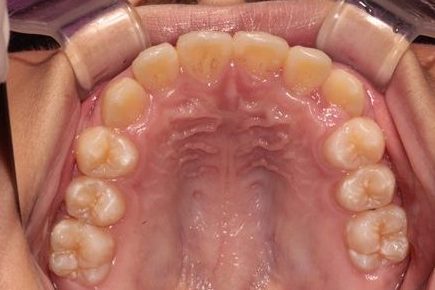

小学校3年生の男の子です。

9才であるにもかかわらず、ガタガタの歯並びをしています。

上下の真ん中もあっていません。

画面右の前歯には生えるスペースがなく、天井(口蓋)から生えています。

2年たち、とりあえずワイヤーを外すことになりました。

すべて永久歯に変わったため、まずは様子見となります。

現在完全に歯並びが完成したわけではありません。